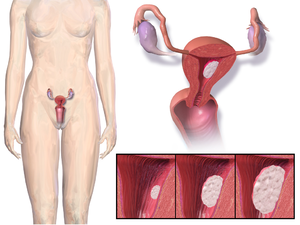

يخفف علاج تعويض الهورمونات من أعراض انقطاع الحيض عن طريق استعادة مخزون الجسم من الإستروجين. ولكن على كل حال، فإن تناول الإستروجين لوحده سيزيد من خطر إصابة المرأة بسرطان الرحم، وهو العضو الذي ينمو بداخله الطفل. ولتقليل هذا الخطر، يصف الأطباء الإستروجين مع البروجسترون للنساء اللائي لديهن أرحام. وفي حالة استئصال رحم المرأة قد يكتفي الأطباء بوصف الإستروجين لوحده.

Endometrial cancer